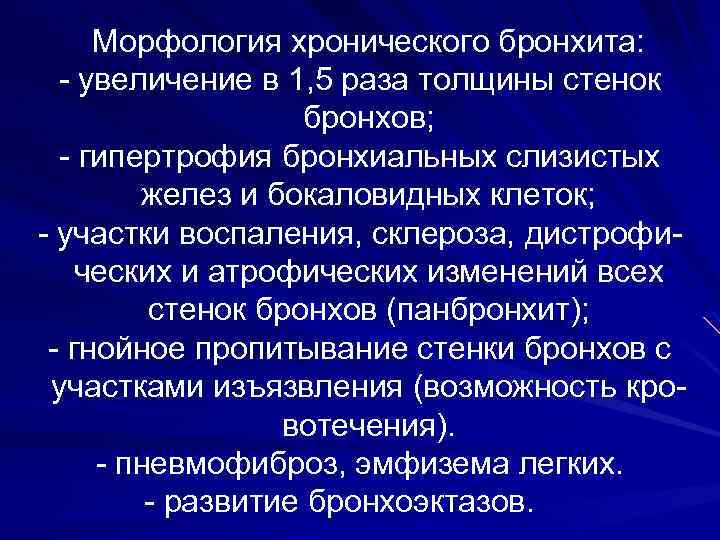

Морфология хронического бронхита: - увеличение в 1, 5 раза толщины стенок бронхов; - гипертрофия бронхиальных слизистых желез и бокаловидных клеток; - участки воспаления, склероза, дистрофических и атрофических изменений всех стенок бронхов (панбронхит); - гнойное пропитывание стенки бронхов с участками изъязвления (возможность кровотечения). - пневмофиброз, эмфизема легких. - развитие бронхоэктазов.